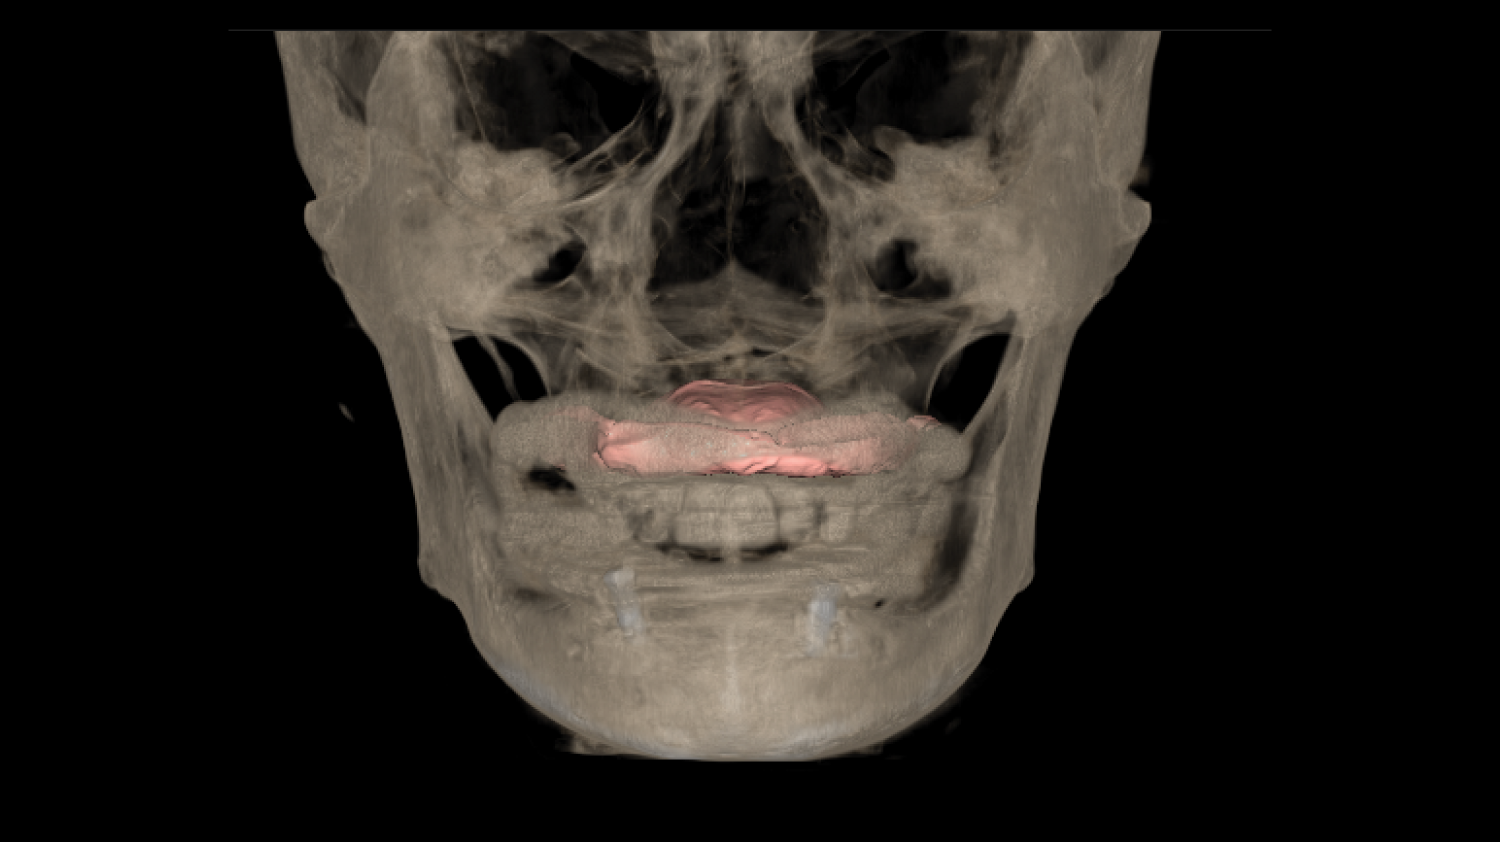

Course Overview

This course presents simplified yet clinically precise workflows for edentulous patients, enhancing both efficiency and patient comfort. Using the JB Tray, participants will learn how to combine custom tray fabrication, final impression, and jaw relation records in a single appointment, supported by digital processing and a live demonstration.

The program also introduces the JB Fork system, which integrates CBCT imaging and anterior reference points to enable one-step surgical stent fabrication without repeated impressions. Through practical demonstrations, attendees will see how this approach streamlines implant surgery while maintaining accuracy. The course concludes with insights into plasma surface treatment in implantology, highlighting its role in advancing clinical outcomes.

• One-Step Surgical Stent Fabrication Using JB Fork and CBCT.

Director’s Clinical Cases

Director’s Clinical Cases

One-Step Surgical Stent Fabrication with JB Fork

• Radiopaque JB Fork and the role of six anterior reference points: Registration with CBCT and integration with facial scanners

• One-step avatar creation without additional clinical procedures

• Surgical stent design and its application in implant surgery

• Live demonstration of JB Fork application in a patient case

Real patient application and taking CBCT, JB fork scanning(Prof Huh) |

Surgical stent design with all guides and implant studio software. (Prof Huh) |

One-Step Surgical Stent Fabrication with JB Fork

• Radiopaque JB Fork and the role of six anterior reference points: Registration with CBCT and integration with facial scanners

• One-step avatar creation without additional clinical procedures

• Surgical stent design and its application in implant surgery

• Live demonstration of JB Fork application in a patient case

Real patient application and taking CBCT, JB fork scanning(Prof Huh)

Surgical stent design with all guides and implant studio software. (Prof Huh)